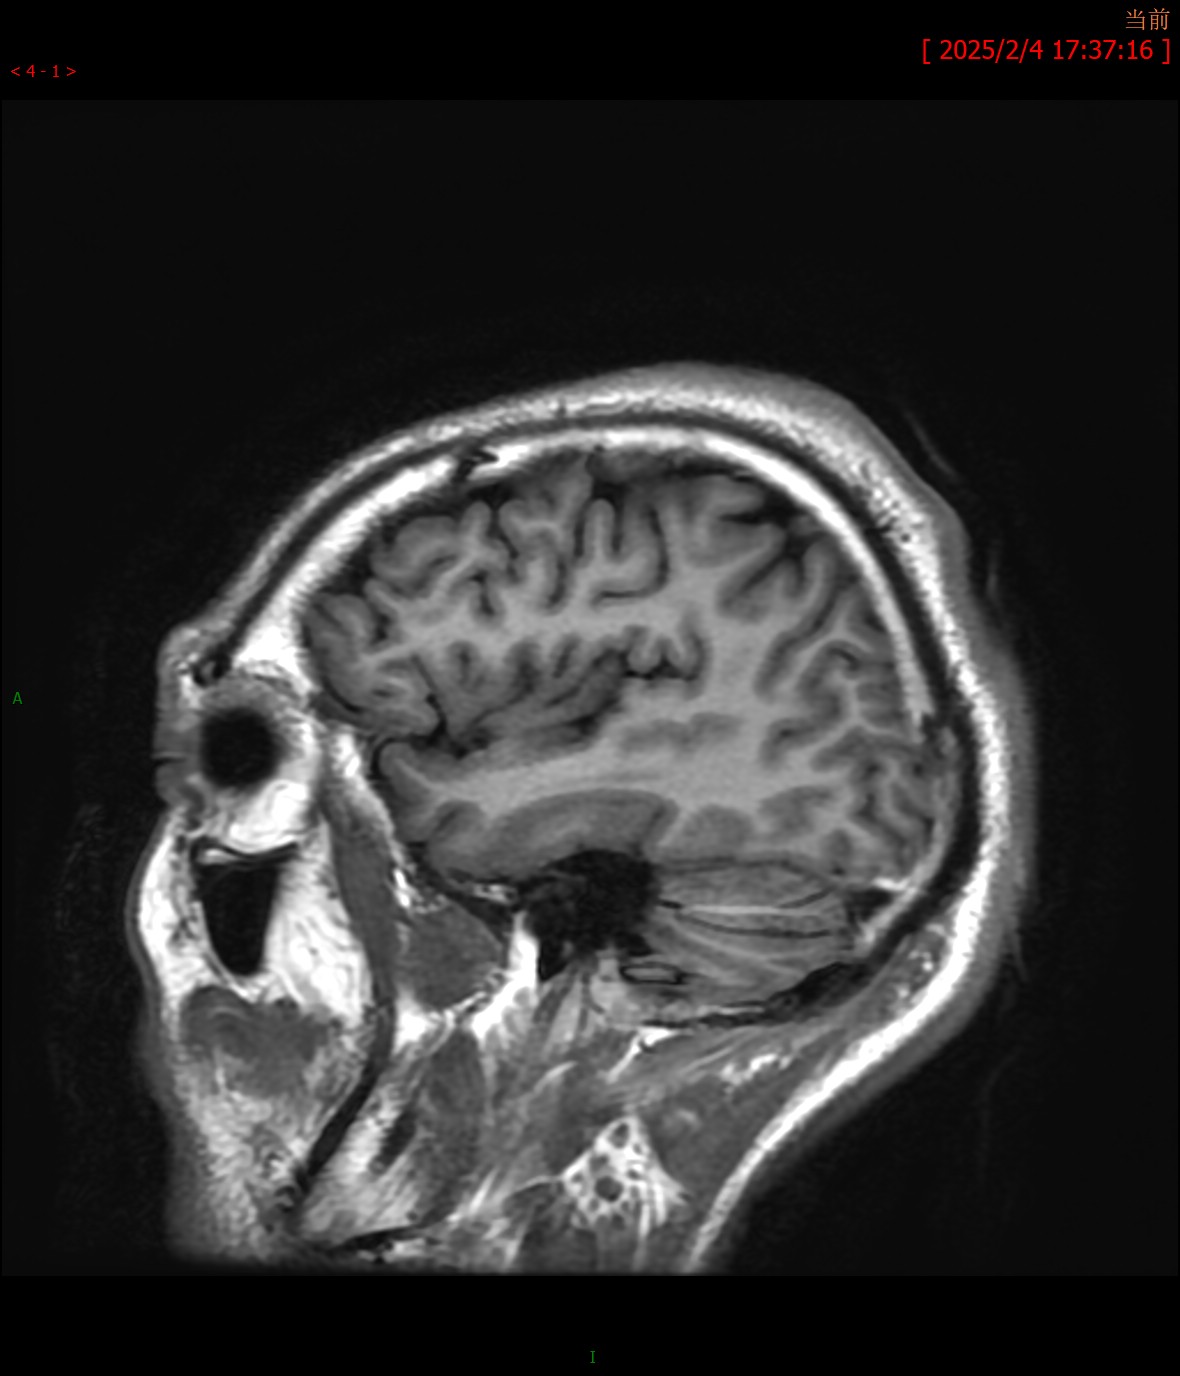

T1WI横轴位 T1WI矢状位

MRA颅脑MR平扫:双侧桥臂、右侧小脑半球、延髓、桥脑、中脑、双侧豆状核、壳核可见多发斑片状稍长T1、T2信号,边界不清,病灶于T2FLAIR呈高信号,大致呈对称性分布。脑室系统轻度扩大,脑沟、脑裂增宽,中脑、小脑体积缩小,中线结构未见移位。

影像学诊断:1. 双侧桥臂、右侧小脑半球、脑干及基底核团多发异常信号伴脑萎缩改变,符合肝豆状核变性颅脑表现;2. 颅脑MRA未见明显异常。

最常见的影像表现为T2WI和T2-FLAIR图像上双侧壳核(70%)、尾状核(60%)、丘脑腹外侧(55%~60%)和中脑(50%)出现对称性高信号,这些区域反映了该病铜沉积的选择易损性特征;有时也可见脑桥(20%)、延髓(10%~15%)和小脑(10%)高信号,大脑白质(25%)和小脑白质(10%)可见局灶性或弥漫性融合状高信号。其机理主要是铜沉积于脑组织中,造成反应性水肿、神经元及胶质细胞缺失、海绵样变性和胶质增生,进而引起不可逆性的空腔和囊变。在未经治疗或治疗效果不佳时,随病程的延长,铜沉积逐渐增多,由于铜顺磁性作用,最终可形成T2WI低信号。T1WI图像上病变信号强度多样,部分病例的受累区表现为低信号,而部分病例则表现为高信号,类似慢性肝性脑病,反映了铜的顺磁性效应。对称性基底节异常信号同时伴有脑干病灶是该病的影像特征。当病变发展到一定程度时,随着神经元及胶质细胞广泛坏死、变性,常出现基底核团及脑干萎缩表现,甚至可出现全脑萎缩。